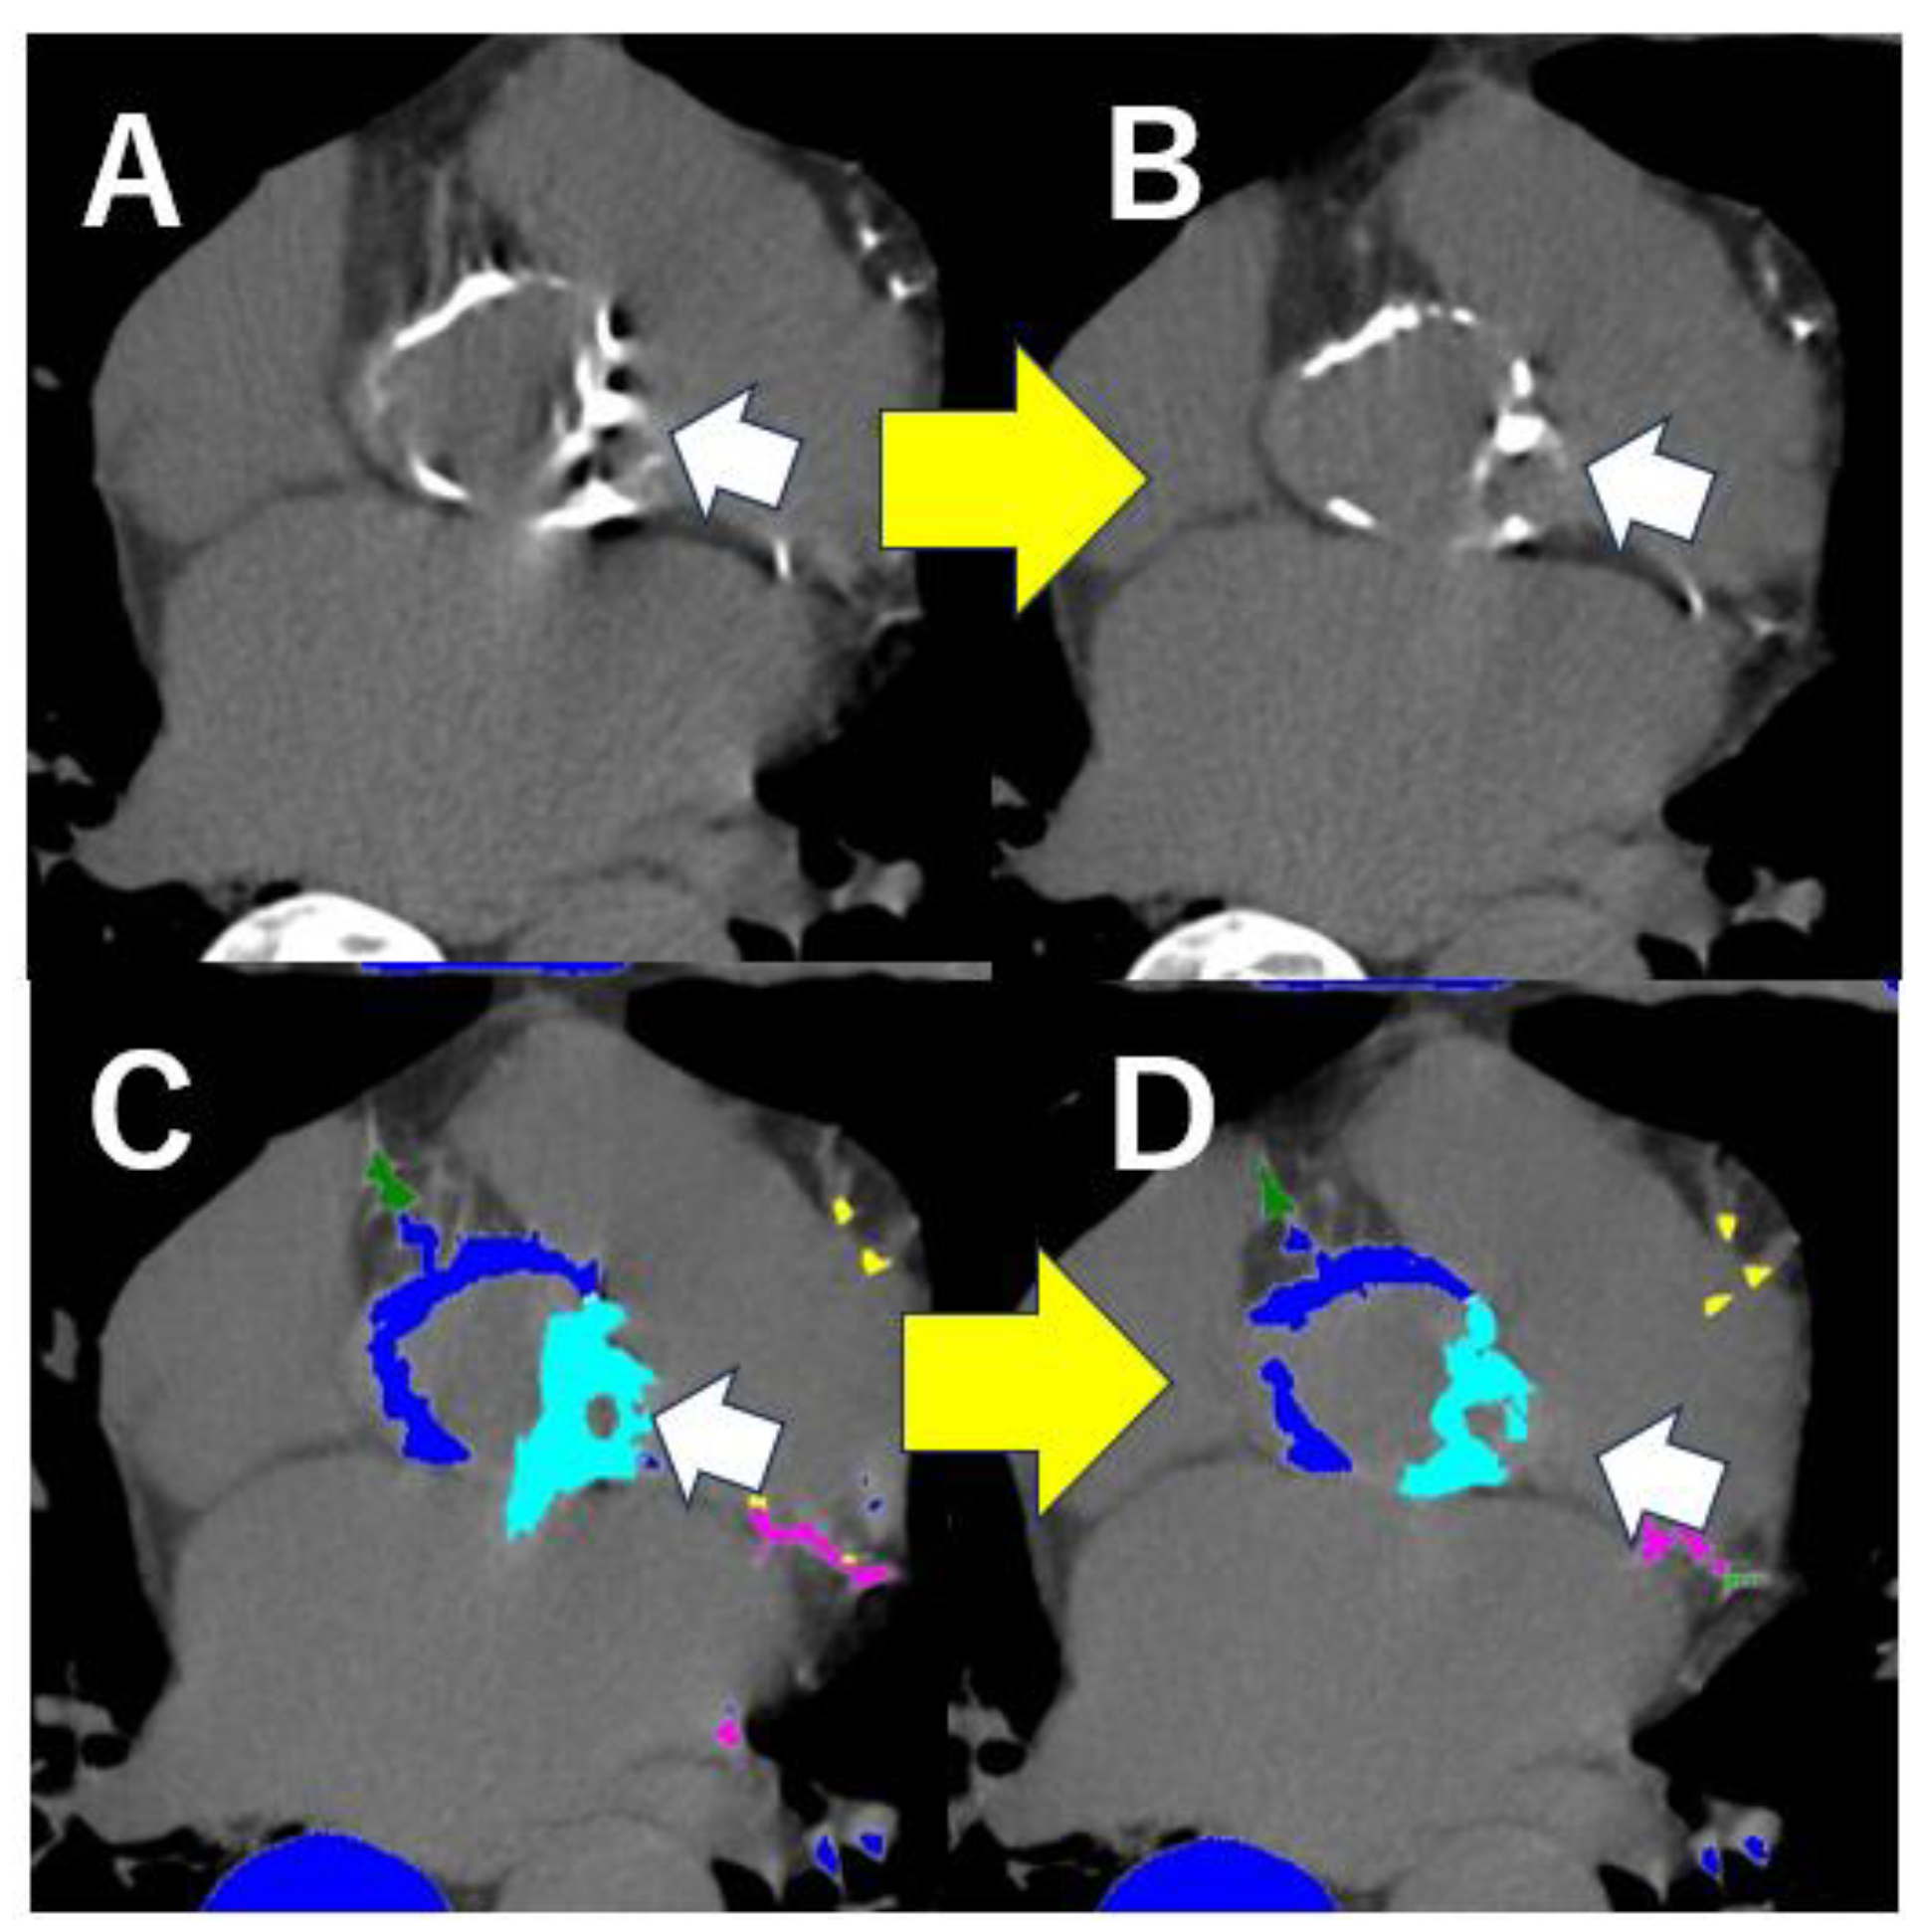

3.3. Computed Tomography for Evaluating the Significance of Aortic Valve Calcification

3.4. Utility of the Evaluation of Congenital Abnormalities on Computed Tomography

- Saito, Y.; Takaoka, H.; Funabashi, N.; Ozawa, K.; Tamura, Y.; Saito, M.; Matsumiya, G.; Kobayashi, Y. A case of very severe aortic stenosis due to unicuspid aortic valve mimicking bicuspid aortic valve with calcification on cardiac computed tomography. Int. J. Cardiol. 2016, 215, 516–518. [Google Scholar] [CrossRef]